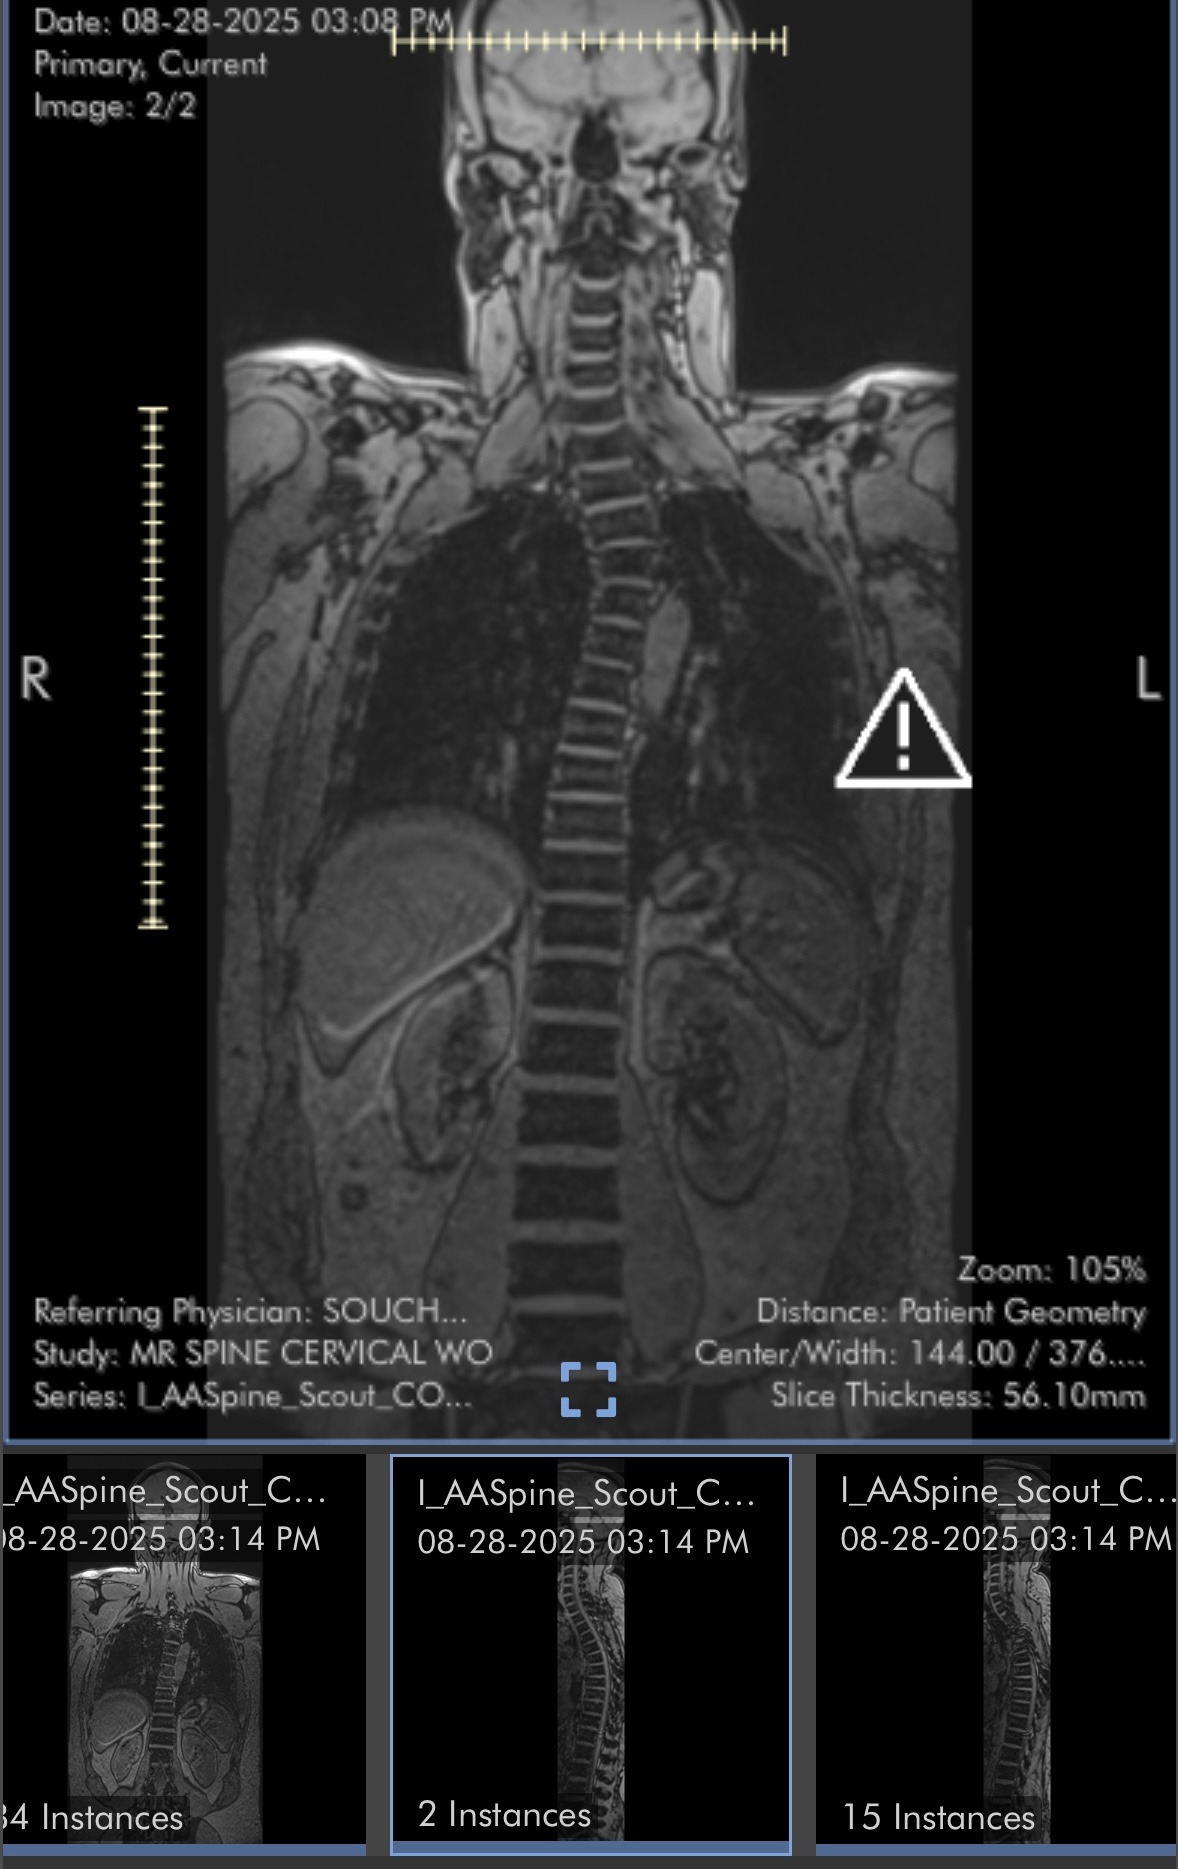

For over 15 years, I’ve been navigating a series of escalating health challenges that have made daily life increasingly difficult. After multiple back surgeries, a diagnosis of fibromyalgia, and a slew of digestive issues, I reached a point where I could no longer continue working. Five months ago, I applied for Social Security Disability, but the approval process has been slow, leaving me in a tough spot both financially and emotionally.